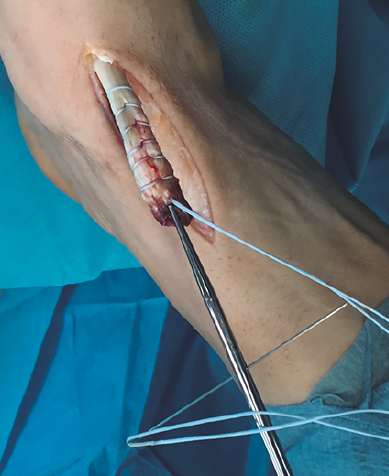

Figura 3. Sutura del tendón tibial anterior con hilo no absorbible.

Se realiza una disección y liberación del TA, resecando la porción distal más degenerada del tendón en forma de punta para introducirlo a través del túnel óseo con mayor facilidad y se sutura con hilo no absorbible (Figura 3), que después pasaremos a través de los orificios de la placa metálica de anclaje extracortical (de dimensiones de 4 × 12 mm).

Figura 4. Preparación de túnel óseo en cuña medial con broca de 4,5 mm y colocación de los hilos en la placa metálica de 4 × 12 mm.

Se realiza túnel con broca de 4,5 mm al nivel de la cortical dorsal de la cuña medial con oblicuidad de proximal a distal hasta llegar a la cortical plantar (Figura 4). Posteriormente, se ensancha el mismo al nivel de la primera cortical según el diámetro del tendón tibial anterior, utilizando una pinza gubia o un avellanador.